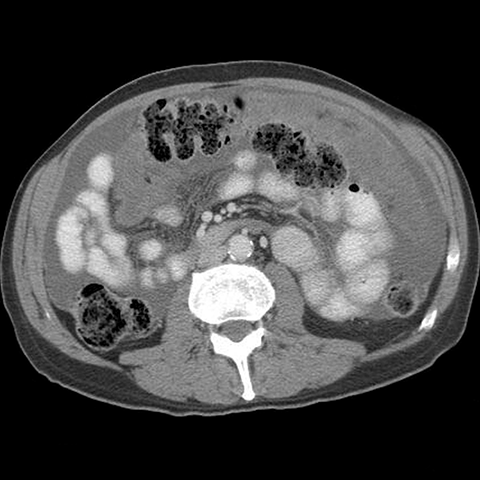

77 year-old woman with a history of ovarian cancer presents with increasing abdominal girth. [5 of 6]